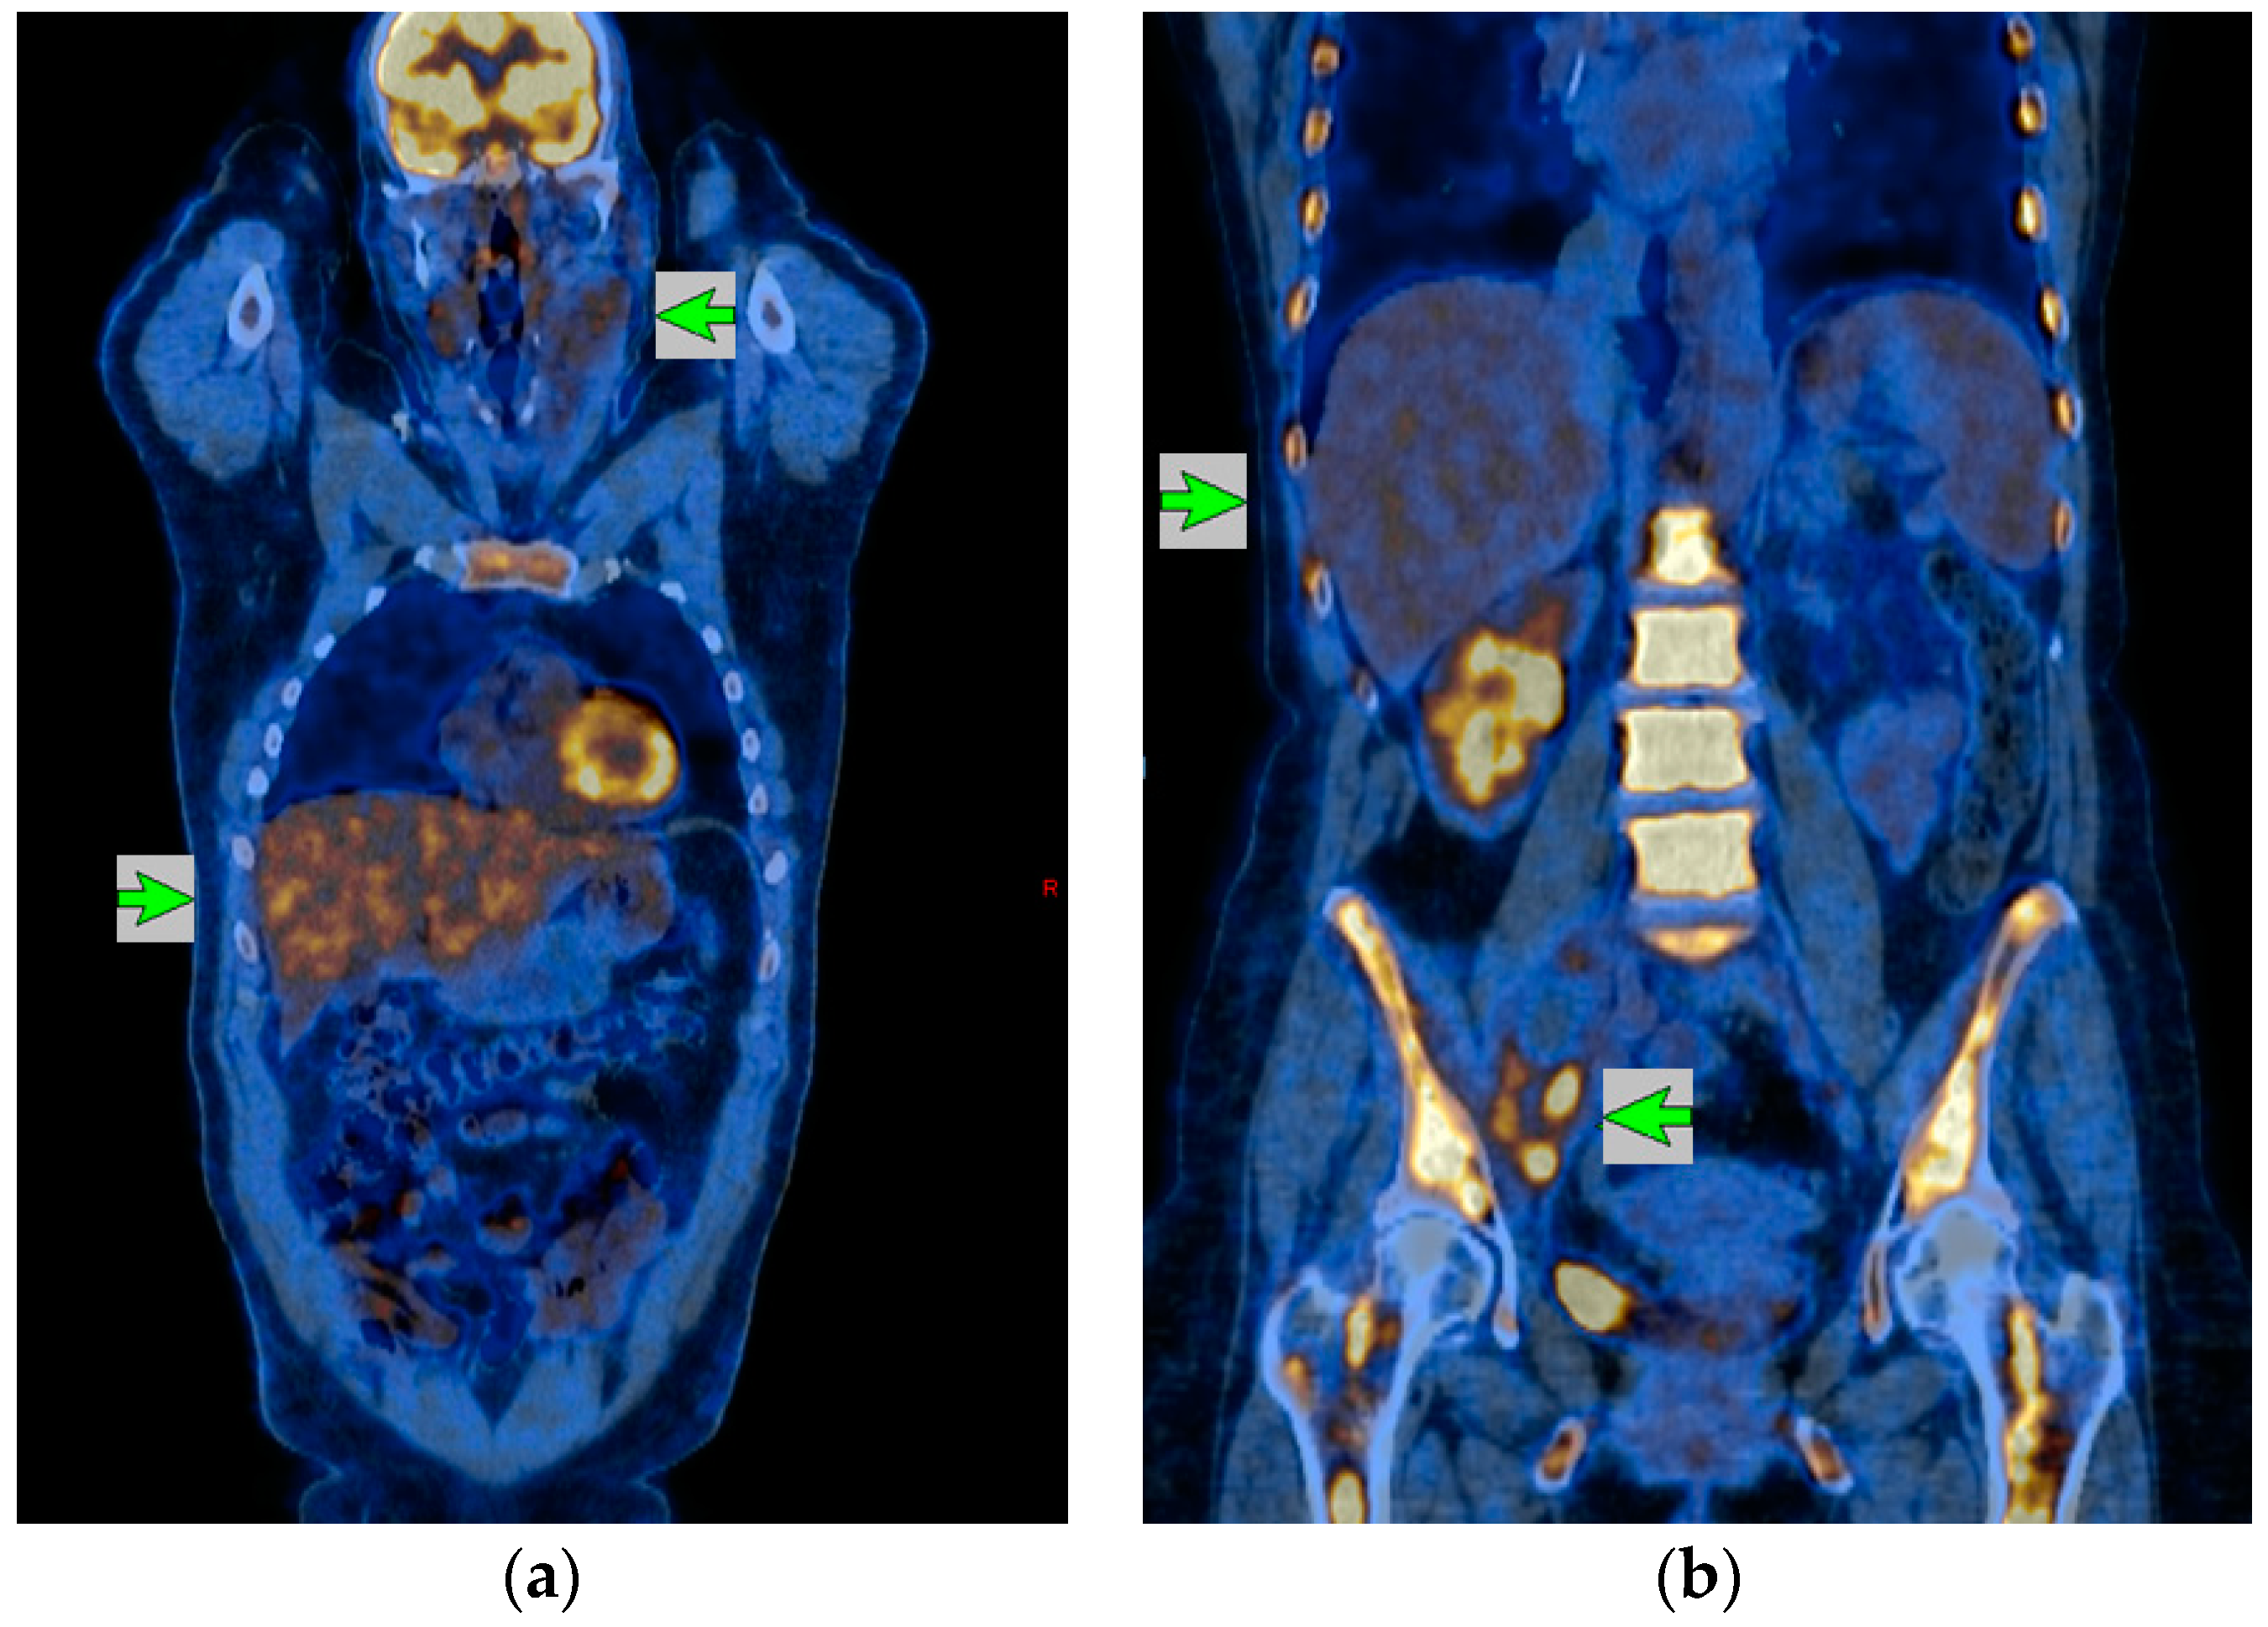

Диагностика лимфомы Ходжкина с помощью ПЭТ и КТ